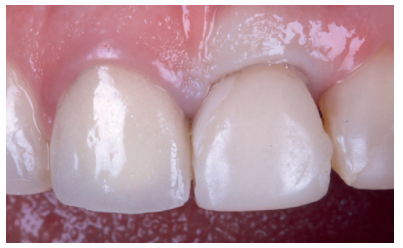

After achieving optimal tissue volume by handling the provisional (Figure 17), an initial scan of the maxilla was performed with the screw-retained provisional crown to obtain the anatomy (Figure 18). Subsequently, a second scan was performed without it, with accurate recording of the gingival contours and the emergence profile achieved (Figure 19), as well as the implant position using the scan body (Figures 20 and 21). For proper recording of the emergence profile, the provisional crown was scanned outside the mouth (Figures 22 and 23); thus avoiding having to perform the classic technique of an individualised transfer17. These records were sent to the prosthetic laboratory, which designed a post-machined sintered metal structure (Figure 24). Once the framework test had been satisfactorily carried out (Figure 25), the colour of the restoration (A2 VITA guide) was taken using a polarised light filter (Figure 26). These records were sent back to the prosthetic laboratory for completion of the implant-retained crown on the printed models (Figures 27 and 28). Prior to the placement of the definitive crown, the emergence profile of the provisional crown was compared with the final one, and the similarity observed between them (Figure 29); thus managing to preserve the profiles maintained from the day treatment was started.

After the 6-month review, excellent stability of all periimplant tissues was verified, with correct volume at the vestibular level, as well as the maintenance of optimal aesthetics and functionality (Figure 30).